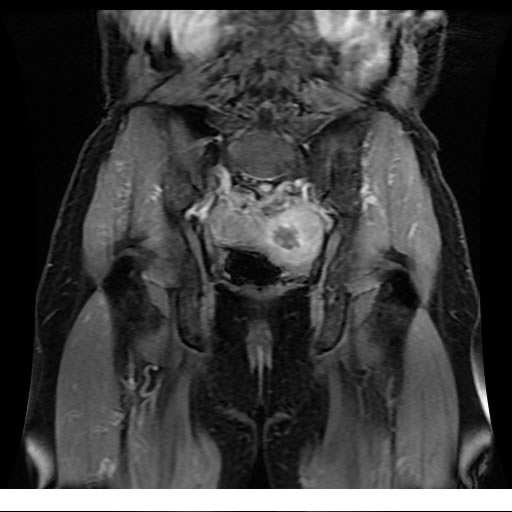

Se realizan adquisiciones en diferentes planos, con secuencias Spin echo y GRE, ponderadas a T1 y a T2, se utilizan pulsos de saturación de grasa y se administra medio de contraste a base de gadolinio.

El útero está en retroversión, retroflexión, y en posición central, se observa liquido en la cavidad endometrial, debido a la presencia de un Ca endometrial; en el anexo derecho se observa una masa quística que mide 3.8 x 2.2 cm de diámetro, corresponde a un quiste bilobulado, posee pared gruesa con componente solido puede tratarse de un Cistoadenocarcinoma, el cual realza con el medio de contraste de forma importante, entra dentro de una clasificación O-Rad tipo IV compatible con un Cistoadenocarcinoma

O-RAD tipo IV, Cistoadenocarcinoma